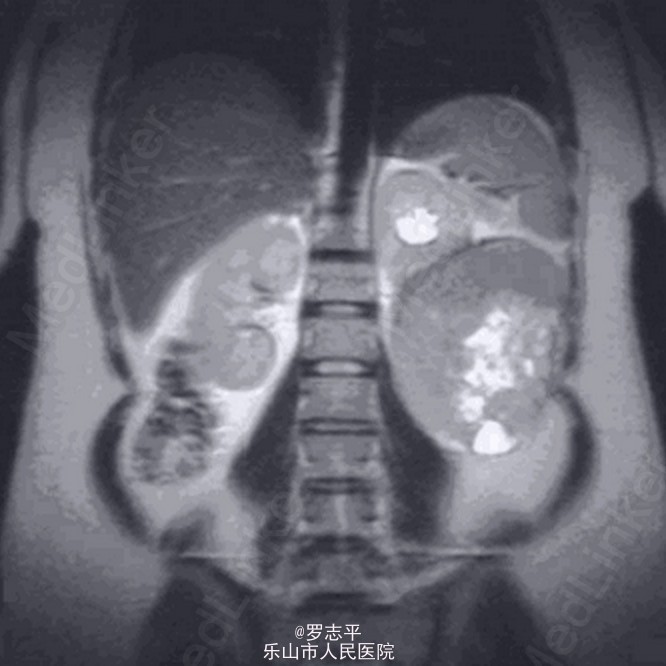

进行超声检查发现左肾不正常的包块。高度提示是肾脏的肿瘤。MRI证实了这些发现,提示在左肾下极有一个边缘锐利,巨大的肿瘤。无淋巴结、远处转移或者左肾上腺侵犯的征象。 患者一般情况良好。家庭史无特殊。肉眼血尿持续存在。此外尿液分析提示中度的蛋白尿,无明显尿路感染的征象。其它的体格检查正常。尤其在患者左肋部未触及包块。患者否认有关妊娠的其它问题。实验室检查在正常限值。